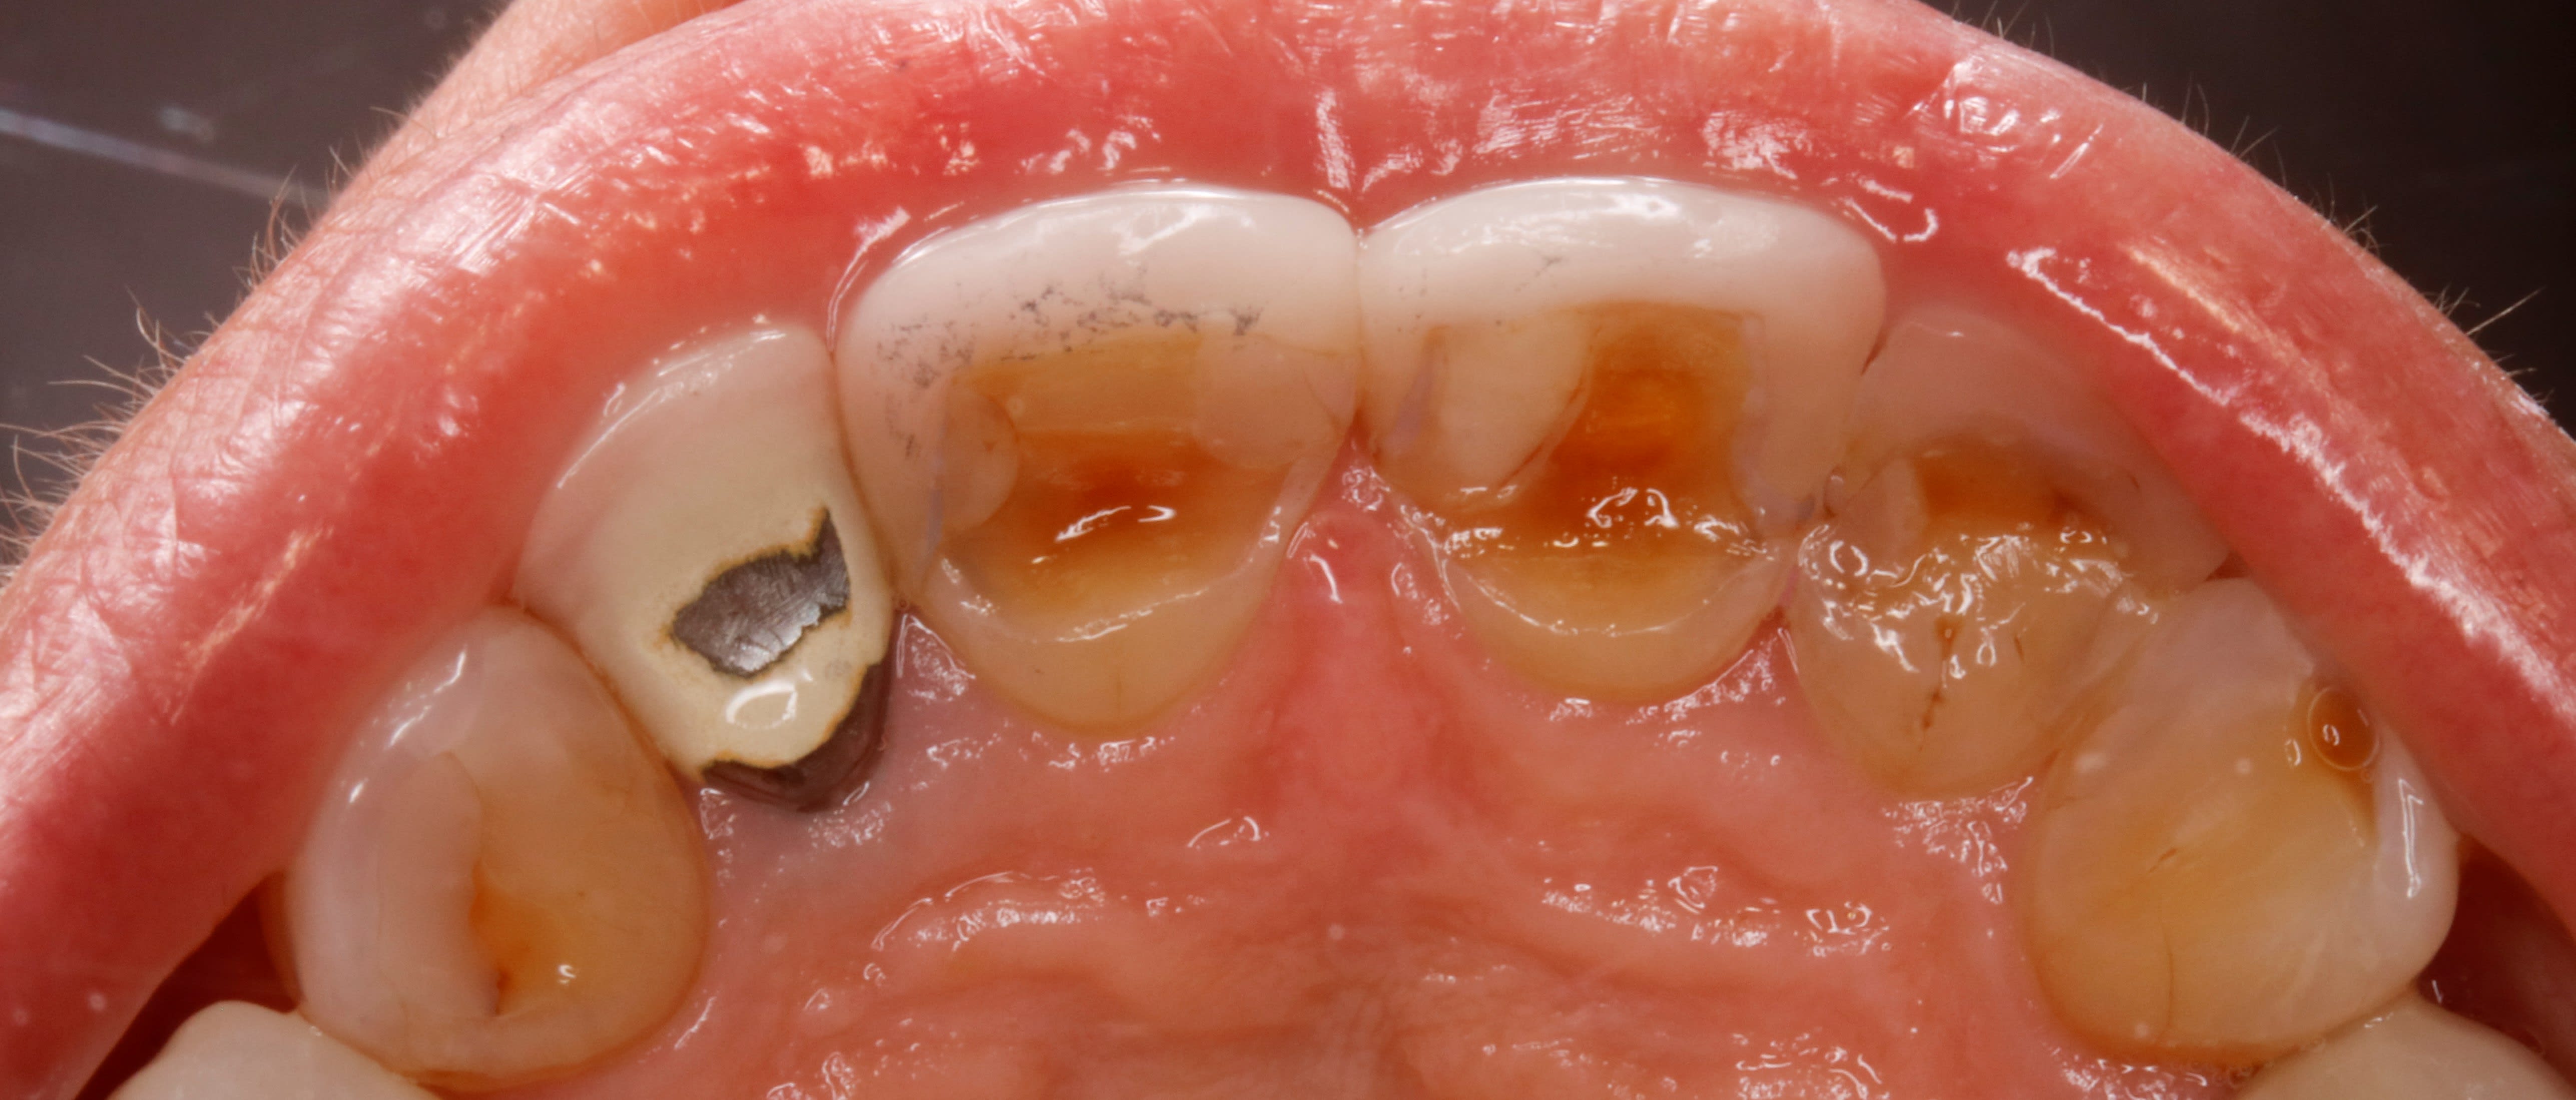

- celle là elle passe son temps à décoller sa facette 12 , qui doit avoir 5 ou 6 ans , et tu sais comme ç est , à force de coller et de recoller , dessous c est tout pourri .

donc elle compte sur moi pour lui faire un truc joli et durable sur sa 12 . et c est là que les ennuis commencent .

La 43 sort d une courbe ideale je lui ferais une prov avec taille complete sur 12 et reproduire l usure cervicale comme sur 11 et 21 et ce qui a ete deja retouché en pal de 22...

mais si tu ne retouches pas la 43 et qu elle balade sa mâchoire en bruxisme lateral tu n auras surement pas trop le choix de la forme de la definive de 12... peut etre pas top

Refaire le bloc 12 à 22 en solidarisant 2/2.

Retoucher le bloc bas pour avoir de l’épaisseur sur les céramiques.

Je suis prêt à parier que les canaux sont loin et donc il faudrait travailler sur dent vivante .

j y vois une supraclusion , de l usure , un passif orthodontique par l absence de PM , une asymétrie des incisives du bas , un sur guidage ant , bref que cette occlusion d aujourd'hui , n est certainement pas celle d'hier et qu il y a bien eu une dérive latérale .

ce qui ne m arrange pas , pcq je n ai pas de place pour faire une couronne sur 12 , la facette n étant plus possible .

Pour moi le problème de la 12 vient aussi de l absence d une incisive mandibulaire. Cela induit une distance inter canine plus petite. Donc la pointe canine se retrouve mesialée par rapport à sa position idéale. Donc elle use a bloc les angle D de son bord libre des incisives latérales maxillaires. Pas de bol c est moche. Su coup elle veut des dents plus longues / plus belles/ mais sans tenir compte de son schéma global de mastication. Du coup ça pète.